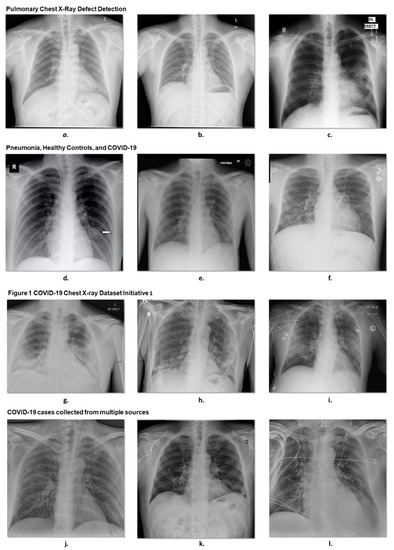

Impartially Validated Multiple Deep-Chain Models to Detect COVID-19 in Chest X-ray Using Latent Space Radiomics

The COVID-19 pandemic continues to spread globally at a rapid pace, and its rapid detection remains a challenge due to its rapid infectivity and limited testing availability. One of the simply available imaging modalities in clinical routine involves chest X-ray (CXR), which is often used for diagnostic purposes. Here, we proposed a computer-aided detection of COVID-19 in CXR imaging using deep and conventional radiomic features. First, we used a 2D U-Net model to segment the lung lobes. Then, we extracted deep latent space radiomics by applying deep convolutional autoencoder (ConvAE) with internal dense layers to extract low-dimensional deep radiomics. We used Johnson–Lindenstrauss (JL) lemma, Laplacian scoring (LS), and principal component analysis (PCA) to reduce dimensionality in conventional radiomics. The generated low-dimensional deep and conventional radiomics were integrated to classify COVID-19 from pneumonia and healthy patients. We used 704 CXR images for training the entire model (i.e., U-Net, ConvAE, and feature selection in conventional radiomics). Afterward, we independently validated the whole system using a study cohort of 1597 cases. We trained and tested a random forest model for detecting COVID-19 cases through multivariate binary-class and multiclass classification. The maximal (full multivariate) model using a combination of the two radiomic groups yields performance in classification cross-validated accuracy of 72.6% (69.4–74.4%) for multiclass and 89.6% (88.4–90.7%) for binary-class classification. Full article

Figure 1